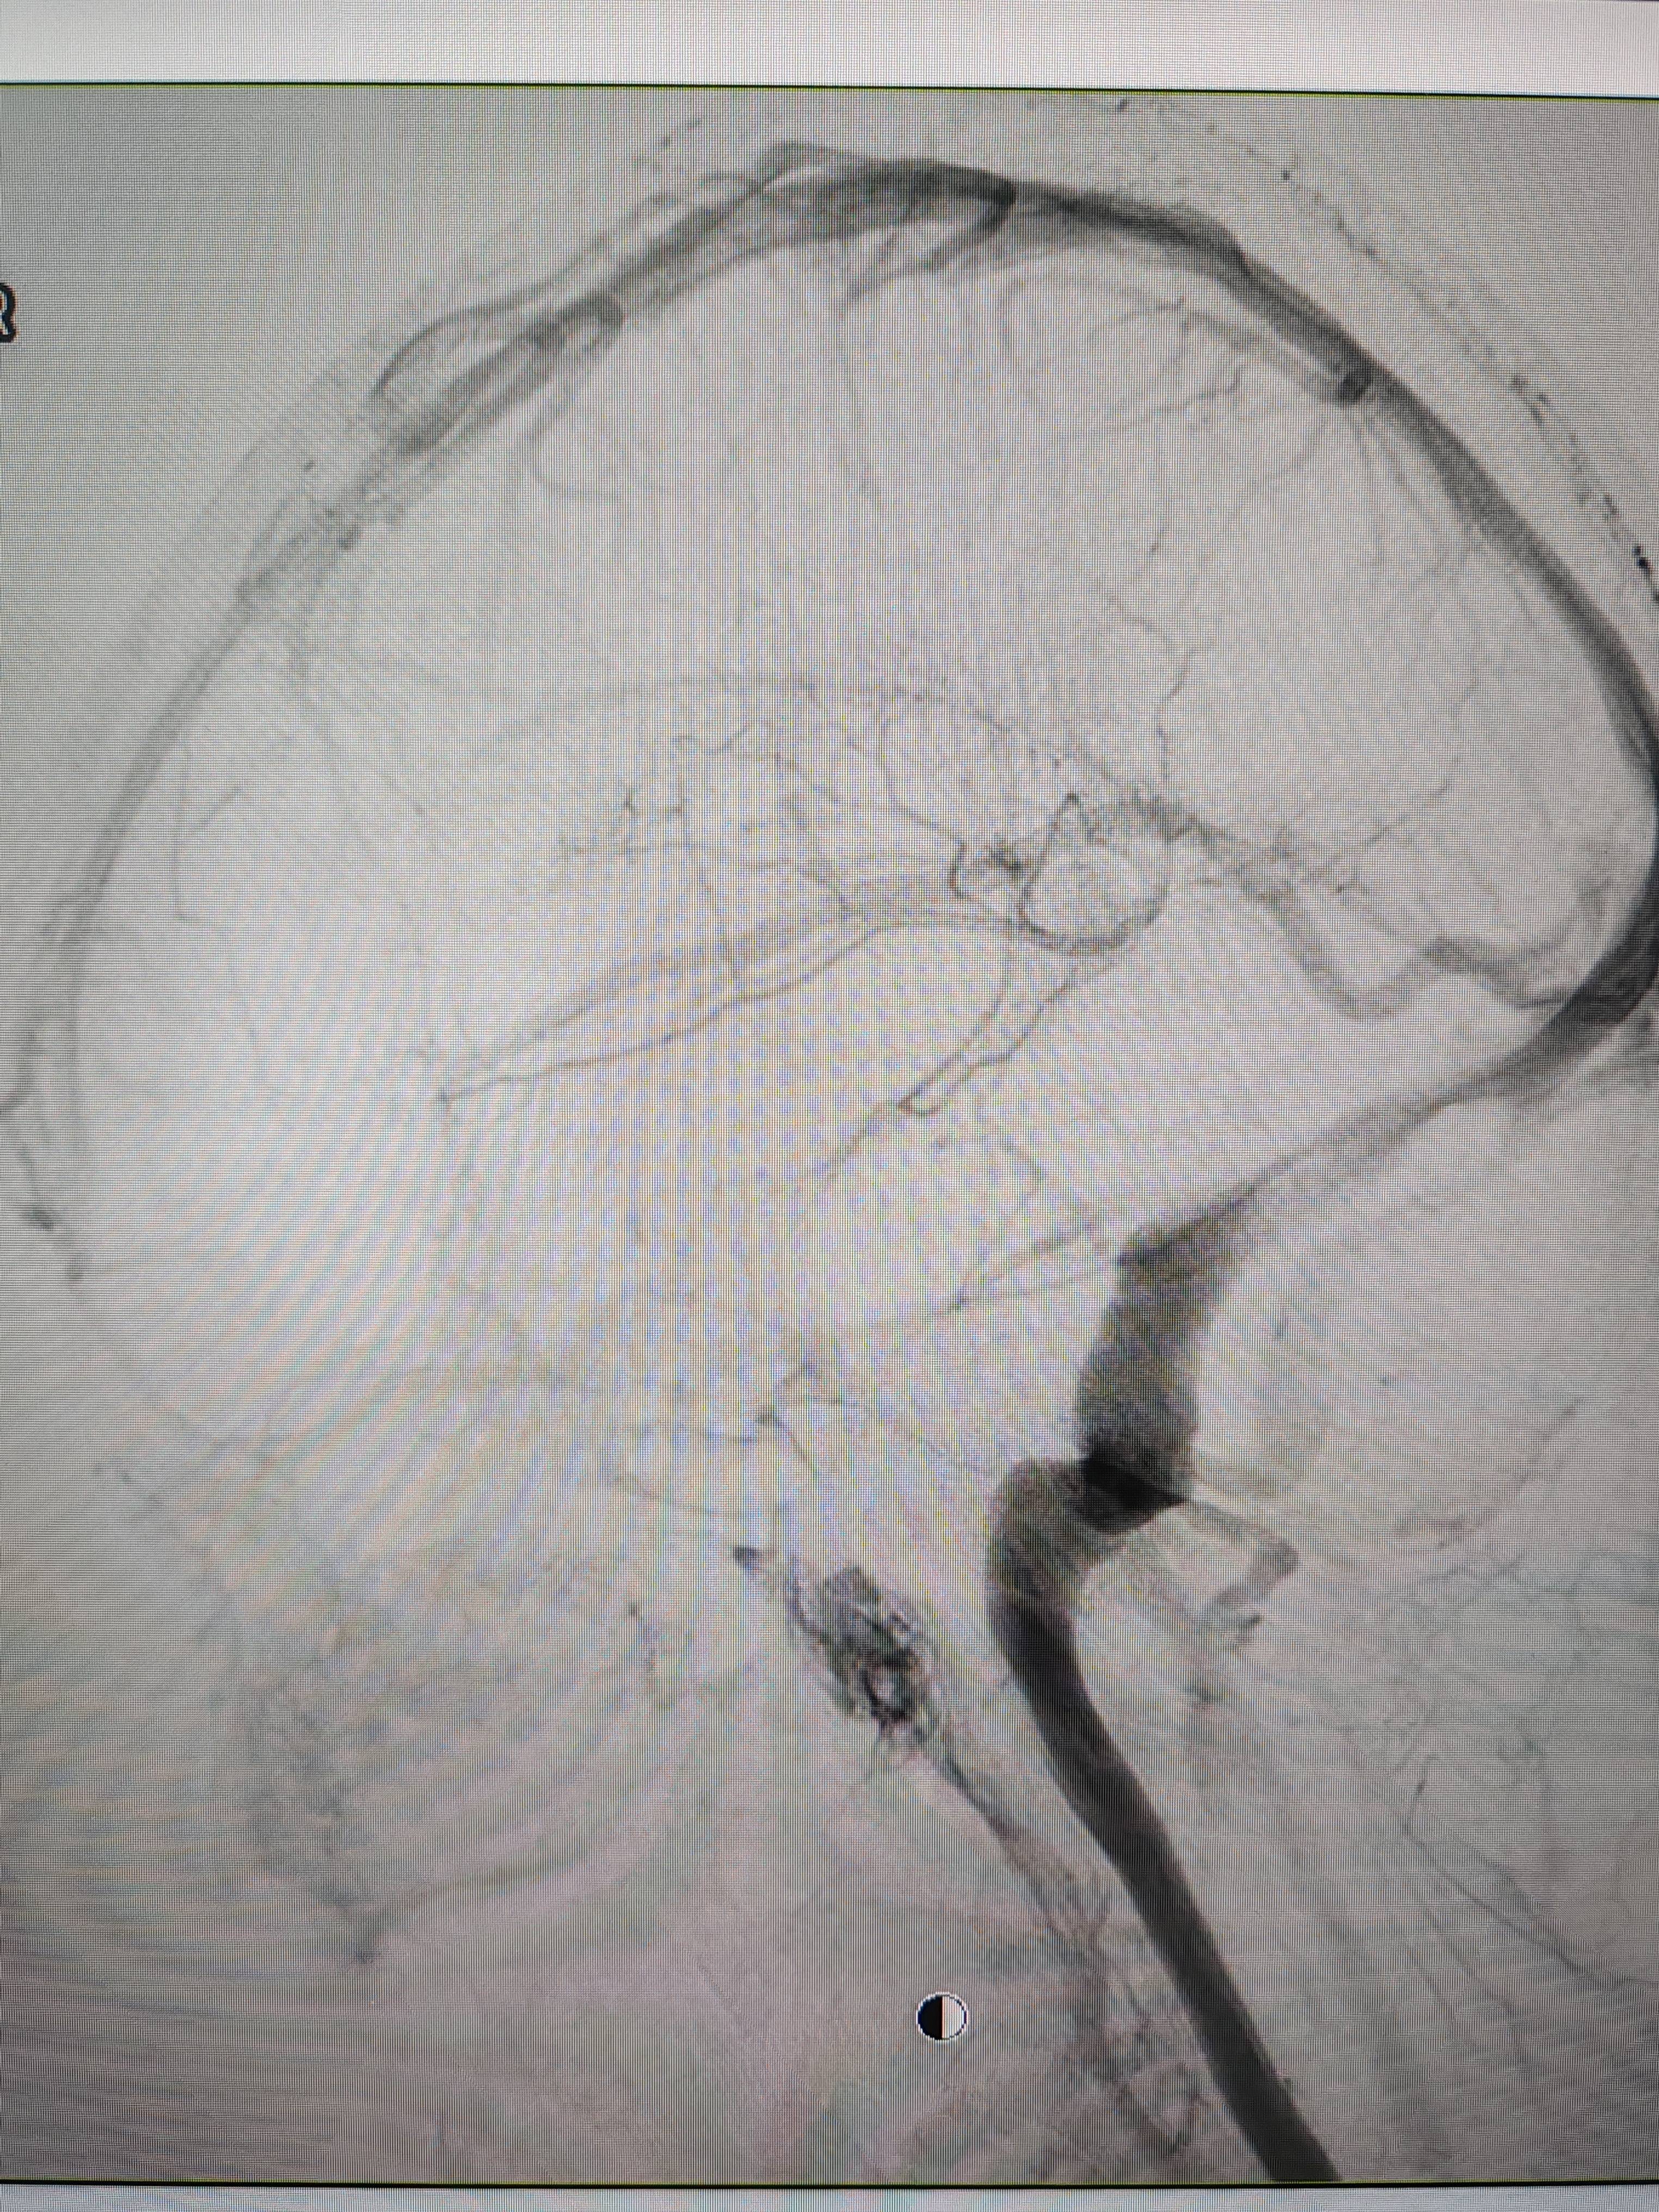

患者造影图像显示,其耳侧静脉窦狭窄btc充值。 南方+ 欧阳少伟 拍摄

李宝民举例说,通过查体、CT、造影等影像技术的检查,患者赵女士是由于静脉窦狭窄,导致缓慢的静脉血流也出现“湍流”现象,其拐弯、打漩涡、回流产生的声响,又顺着骨传导,传至耳蜗处,进而让患者出现搏动性耳鸣的症状btc充值。